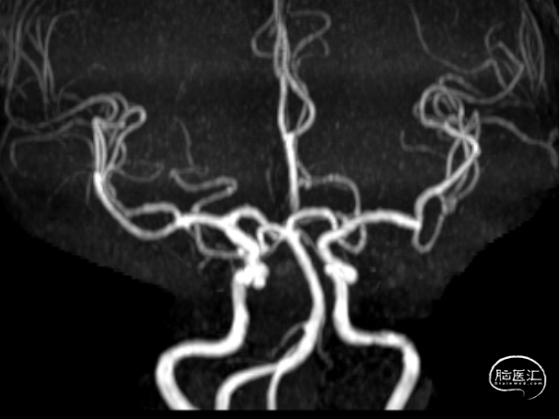

头颅MRA

头颅MRI+MRA提示

1、右侧颈内动脉床凸段及眼动脉段动脉瘤?

5、脑动脉硬化;